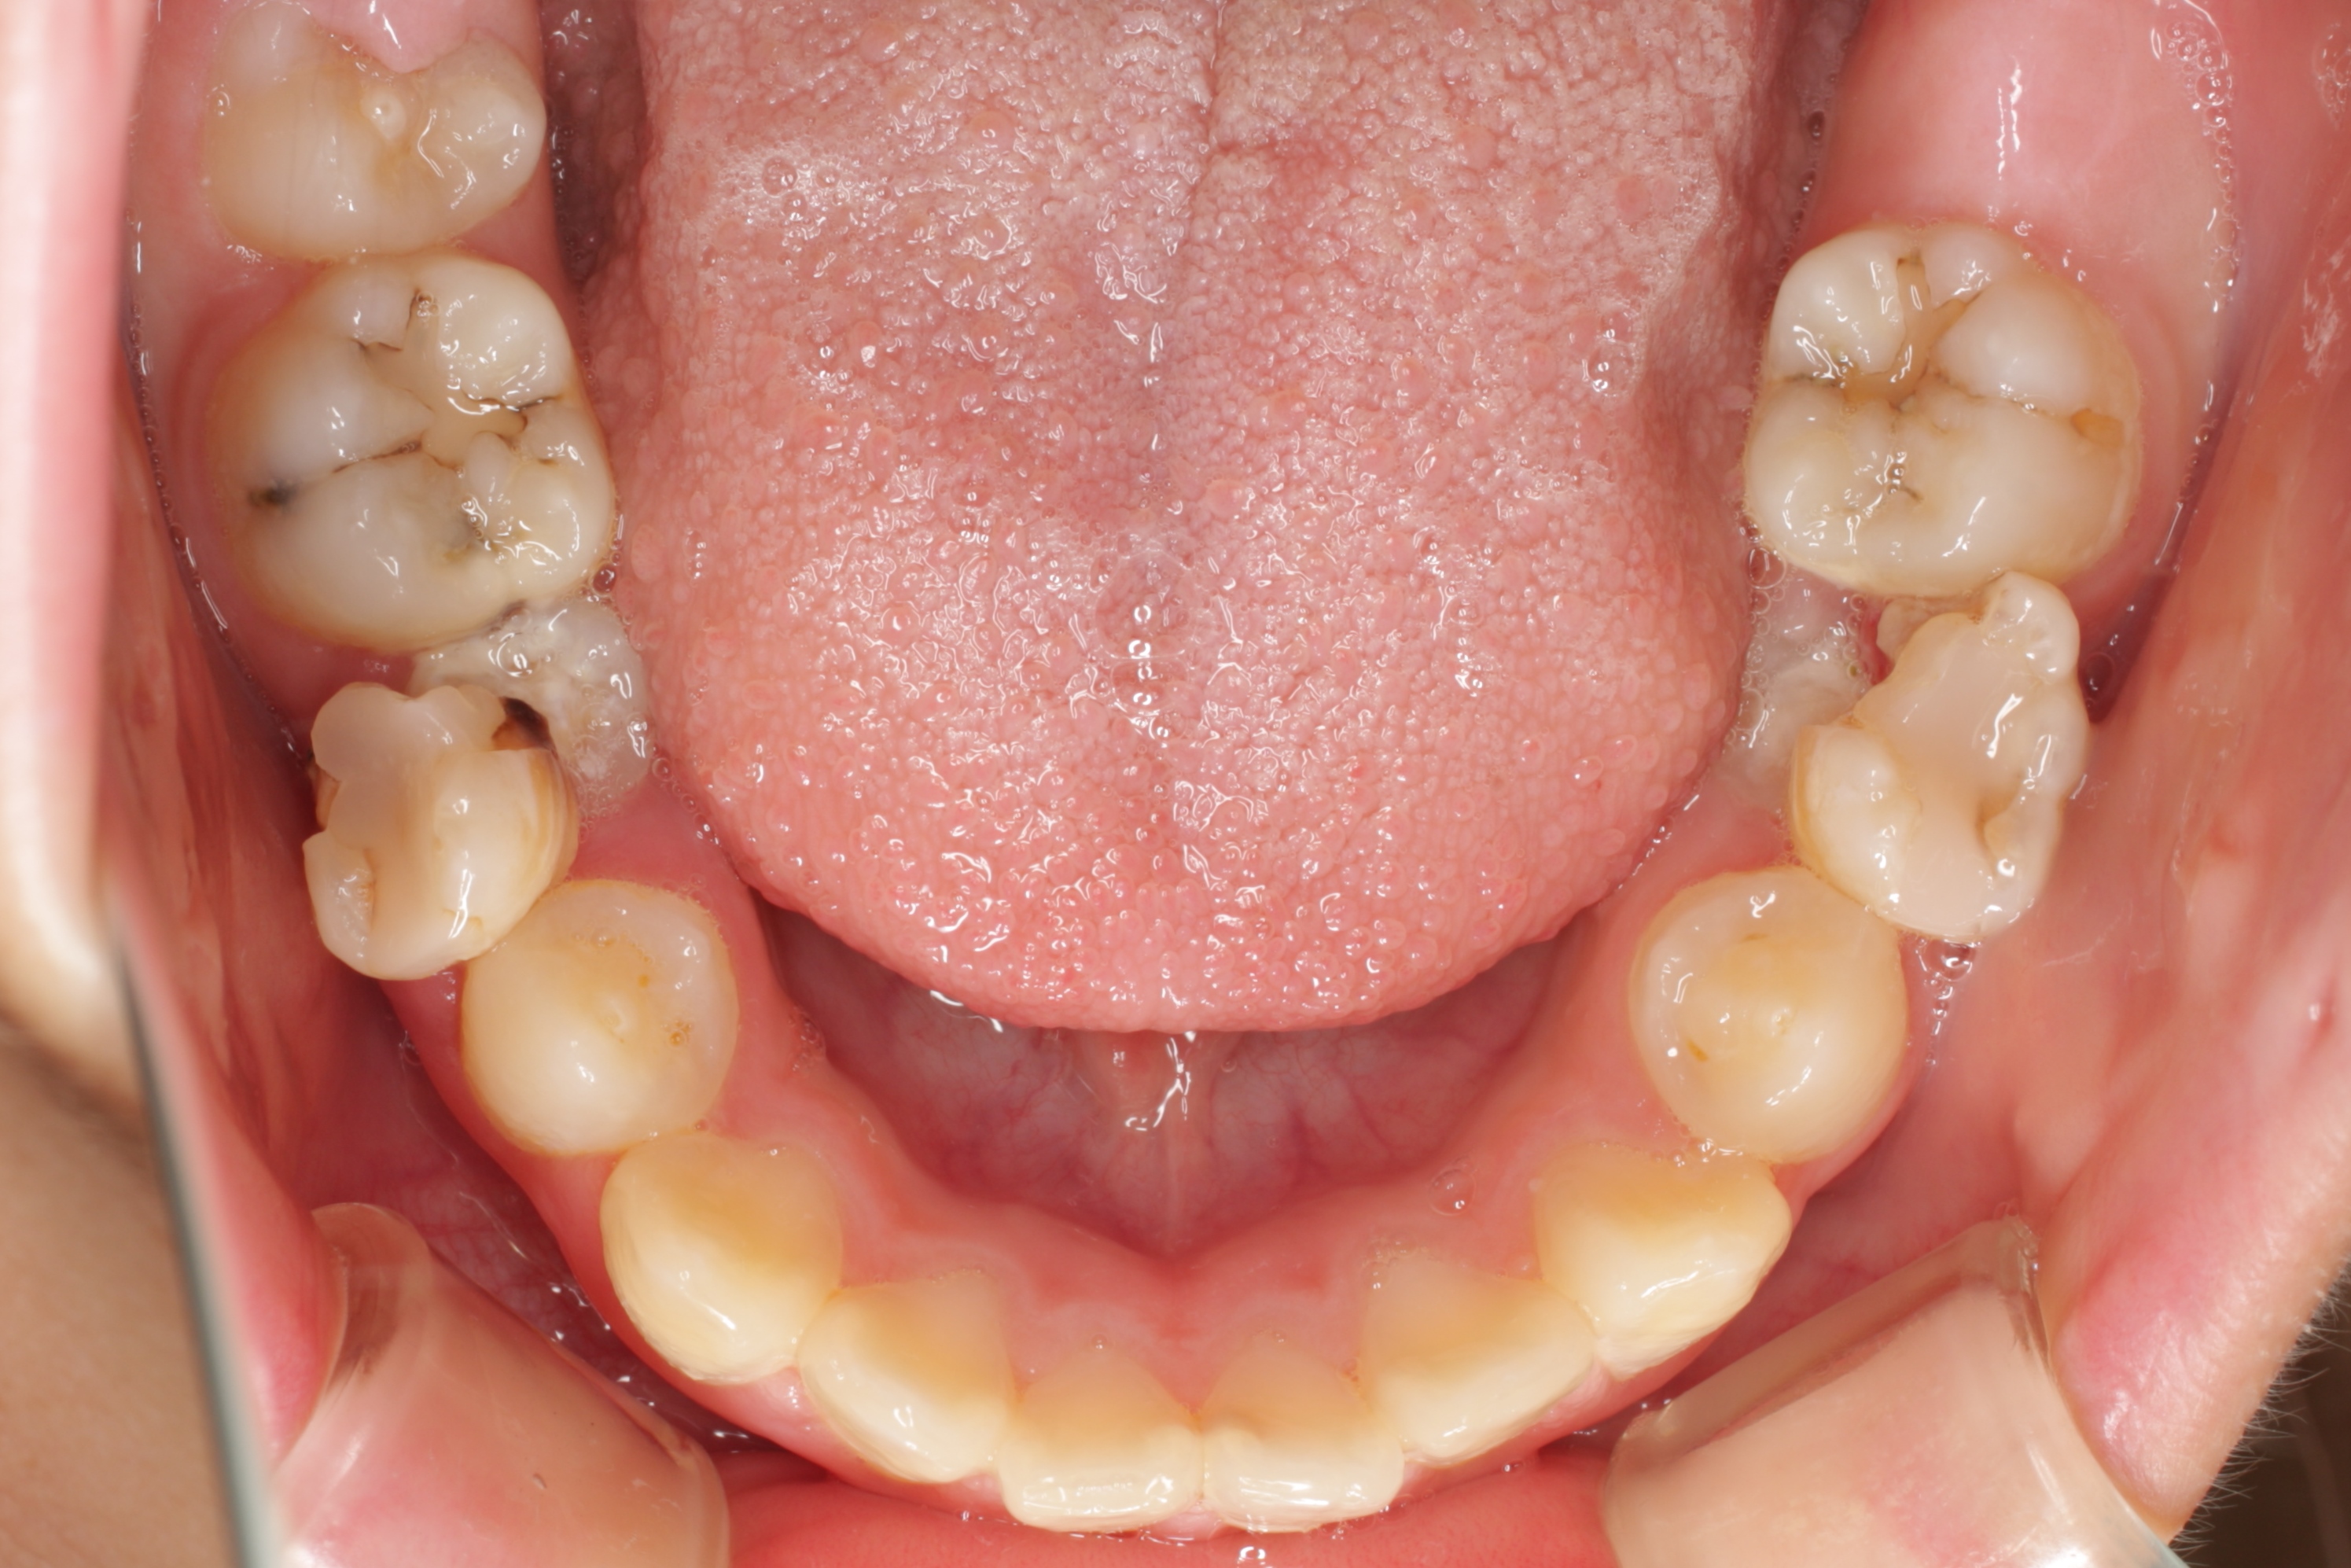

学校健診で虫歯と言われ、来院してくれた子供さんです。とても良い子で、お家の方も感じの良い方です。ただ、気がつくチャンスが無かっただけなのです。歯の大切さと予防歯科の重要性に。

歯科医や学校がもっと予防歯科の普及に頑張らないといけないなと深く反省させられる瞬間です。ごめんなさい。ごめんなさい。

一般的には「何本か虫歯があるので、歯医者に行ってなおしてもらおう」といった感覚なのでしょう。悲しいかな日本ではそれがフツーです。

問題はこの子の家庭に予防歯科の概念と知識が欠如している事なのです。何回も言っているように歯医者に行っても歯は元通りにはなりませんし、修繕が追いつかない程の速度で虫歯ができています。

この子は、これから一生の間に少なくとも100回は歯ぐきに注射をされて、少なくとも300回は通院し、歯を削られたり、神経を抜かれたり、銀歯を入れられたり、そしていつかは歯を抜かれたりするようになります。歯科医師の私にはこの悲しい将来が見えてしまいます。

一日も早く、一人でも多くの方が予防歯科の重要性に気がついて欲しいと思います。そのために私達歯科医療従事者も頑張ります!